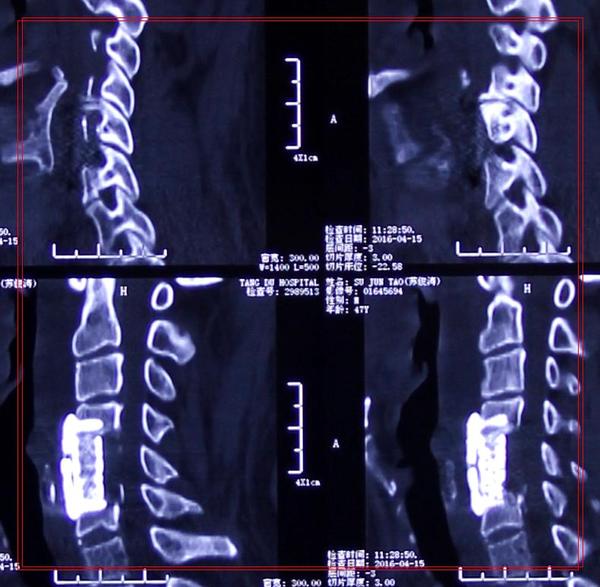

治疗:显微镜下单节段颈椎间盘切除植骨融合内固定术

影像学资料